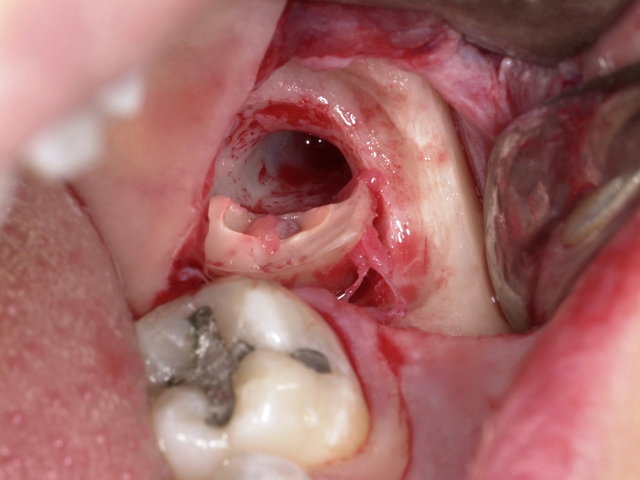

Sichtbarer Nerv im Zahnfach

Operative Weisheitszahn-Entfernung ... ✓

Operative Weisheitszahn-Entfernung ...